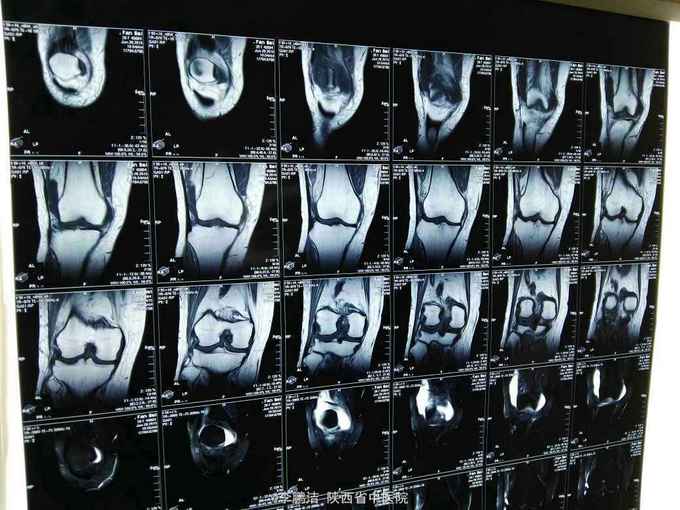

主诉:双膝关节疼痛,间断发作4年余。 现病史:患者于入院4年前因劳累后出现双膝关节疼痛,久行及上下楼梯时疼痛加剧,经休息疼痛好转,故当时未能引起重视,未进行系统治疗。其后因疼痛在当地诊所行局部理疗(具体治疗不详),经治疗后疼痛当时好转。之后,双膝关节疼痛症状时轻时重,间断性发作。近来,双膝关节疼痛症状加重,患者为求进一步治疗,遂于今日来我院就诊,门诊以“膝骨关节病”之诊断收住我科。

查体:脊柱生理弯曲尚可,L3-S1棘突及椎旁无压痛,双膝关节无肿胀,局部皮肤温度不高,内外侧副韧带止点压痛(+),髌韧带止点处压痛(-),鹅足滑囊处压痛(+),浮髌试验(-),髌骨摩擦试验(+),抽屉试验(-),双膝关节活动度明显受限;生理反射存在,病理反射未引出。

中医诊断:骨痹症 气滞血瘀 西医诊断:1、膝骨关节病 2、2型糖尿病 3、高血压 中医治疗方案:中药封包治疗、穴位贴敷舒筋通络。 西医治疗方案:口服阿托伐他汀钙片降脂,盐酸二甲双胍片、阿卡波糖片降糖,苯磺酸左旋氨氯地平片降压,硫酸氨基葡萄糖胶囊保护软骨面;患者夜间出现胸闷、气短,可行动态心电图、活动平板试验排除心脏疾病。 可给予口服活血化瘀,行气宽中之中药汤剂,具体方剂如下: 生地黄25g 当归10g 川芎15g 桃仁10g 红花10g 赤芍15g 柴胡10g 枳壳10g 怀牛膝15g 桔梗10g 生甘草6g 黄连10g 半夏(清半夏)15g 瓜萎15g 山栀10 7付水煎服 一日一剂